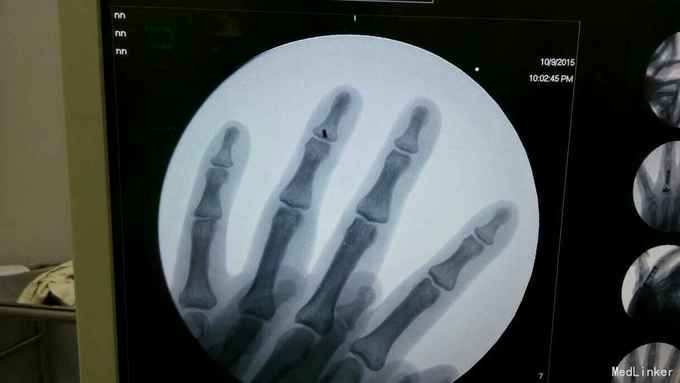

患者外伤后手指末节主动屈曲不能1周

查体可见左环指末节主动屈曲不能,被动活动正常,被动伸直时无阻力,休息位时远指间关节过伸

指深屈肌腱断裂,行指深屈肌腱止点重建,术中可见指深屈肌腱自止点处断裂,术中切开腱鞘,暴露指深屈肌腱断端,有回缩,空针头固定肌腱断端,铆钉自远节指骨基地打入,缝合肌腱断端